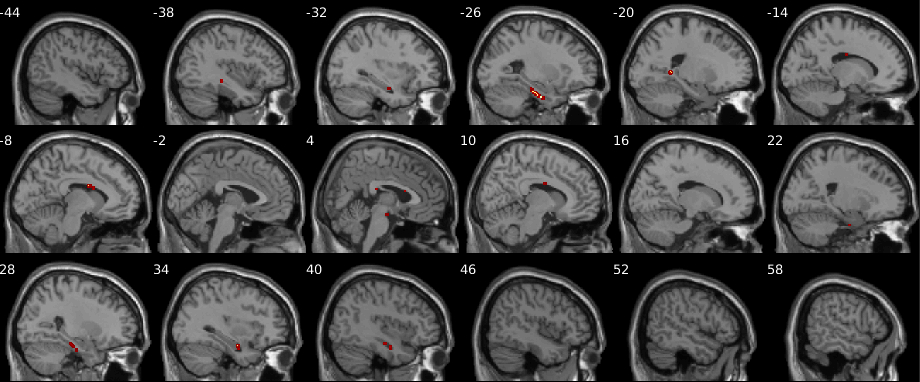

The test statistics obtained using the original data labels whose value exceed the -threshold associated to a given -value will correspond to the null hypothesis rejected. Figure 8 shows the resultant mapping between -threshold and -values for the max null distribution for a given set of hyperparameters. It is evident that the difference across methods is minimal. Moreover, Figure 8 shows that low -values (), which are the main object of interest, show the lowest differences. However, despite the low percent differences between the -values, in the larger datasets (, , and subjects) RapidPT consistently yields slightly more conservative -values near the tails of the distribution. Nonetheless, Figure 11 shows that the resampling risk between RapidPT and the two baselines remains very close to the resampling risk between both baselines. In practice, these plots show that RapidPT will reject the null hypothesis for a slightly lower number of voxels than SnPM or NaivePT.

Despite the slight difference in thresholds, the actual brain regions whose null hypotheses were rejected consistently match between both methods as shown in Figures 9 and 10. Additionally, the regions picked up by both RapidPT and SnPM in Figure 9 correspond to the Hippocampus – which is one of the primary structural brain imaging region that corresponds to the signature of cognitive decay at the onset of Alzheimer’s disease. The regions in Figure 10 contain a subset of the brain regions in Figure 9 which is expected from the thresholds shown in the right column of Figure 7.

ADNI Statistic Maps